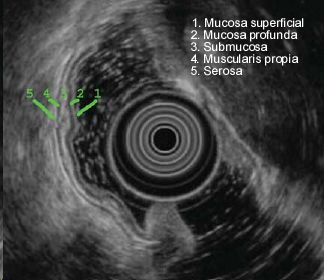

Se expone un video de ecoendoscopia radial (USE radial) de un lipoma en la 2ª porción duodenal. Los lipomas son tumores benignos que se originan en la submucosa. En la ecoendoscopia, con una frecuencia de 7.5 Mhz, la submucosa es la tercera capa de las 5 que se observan y está situada bajo la mucosa profunda(capa 2). Es hiperecogénica. Por ello, los lipomas suelen apreciarse como una lesión homogenea, redondeada e hiperecogénica, dependiente de la 3ª capa. Con estos datos endosonográficos, junto al aspecto amarillento y el signo de la almohada (hundimiento de la lesión al presionar con un fórceps de biopsia) durante la endoscopia digestiva alta, el diagnóstico de lipoma es prácticamente seguro, no siendo necesaria la punción y el estudio histológico.